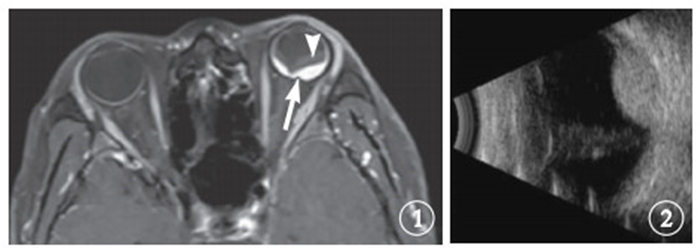

末次隨訪時,腫瘤體積1.24~2.16 cm3,腫瘤體積中位數1.68 cm3,腫瘤平均體積(1.68±0.30) cm3。與治療前比較,治療后腫瘤體積縮小14.6%~72.7%,平均縮小(44.89±21.30)%(圖 3,4)。

末次隨訪時,腫瘤體積1.24~2.16 cm3,腫瘤體積中位數1.68 cm3,腫瘤平均體積(1.68±0.30) cm3。與治療前比較,治療后腫瘤體積縮小14.6%~72.7%,平均縮小(44.89±21.30)%(圖 3,4)。